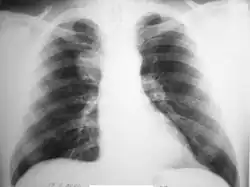

На рентгенограммах гамартомы с внутрилёгочной локализацией имеют вид одиночных (гораздо реже — множественных) шаровидных теней (солитарных лёгочных узлов) с чёткими, слегка волнистыми контурами[19]; при дольчатом строении очертания опухоли могут быть бугристыми. Характерны известковые включения, расположенные в виде отдельных зёрен или же в виде центрального конгломерата. Часто интенсивность тени центральной части опухоли значительно выше, чем краевых отделов (отличительная особенность гамартомы от других опухолей). Лёгочный рисунок вокруг гамартомы, как правило, не изменён[24]. Иногда имеется ободок по периферии (ложе опухоли). Характерно отсутствие изменений в корне лёгкого и плевральных реакций. При длительном динамическом наблюдении размеры гамартомы изменяются крайне медленно, но часто прогрессирует интенсивность известковых отложений[6][20].

В связи с особенностями рентгенологических проявлений выделяют 4 варианта гамартом:

- Гамартомы с неправильной, шаровидной или овальной формой, чёткими гладкими или же бугристыми контурами, имеющие весьма высокую интенсивность тени, которая уменьшается к периферии гамартомы. Характерны хорошо видимые на прямых и боковых рентгенограммах точечные, пятнистые и линейные обызвествления, которые сливаются в единый конгломерат.

- Гамартомы средней интенсивности, имеющие резко очерченные гладкие или бугристые контуры и хаотичное отложение глыбок извести в толще опухоли.

- Гамартомы с единичными или множественными очагами обызвествления, располагающимися как в толще гамартомы, так и по её периферии.

- Гамартомы без обызвествления[6].